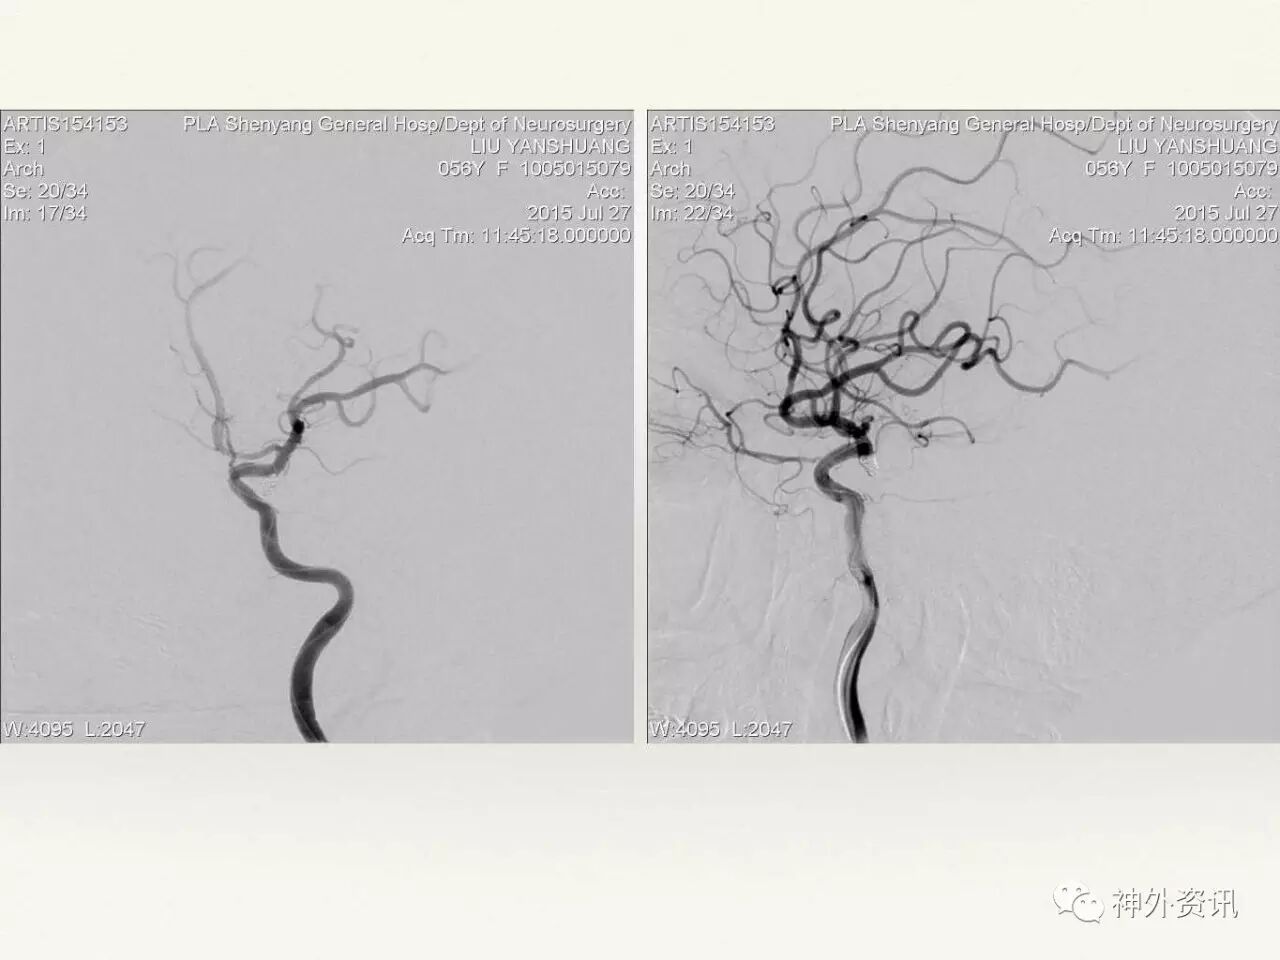

在东北地区率先开展了颈内动脉、大脑中动脉及基底动脉闭塞血管内再通、颅内动脉栓塞急性期取栓、血流导向装置治疗大型宽颈动脉瘤等,对颅内动脉瘤、动静脉畸形、颈动脉及颅内动脉狭窄、颈内动脉海绵窦瘘、硬脑膜动静脉瘘等外科治疗具有较深的造诣。完成脑血管造影8600余例,各类脑血管病介入手术共4500余例,动脉瘤、动静脉畸形、脑肿瘤、脑出血及脑外伤等外科手术1500余例。